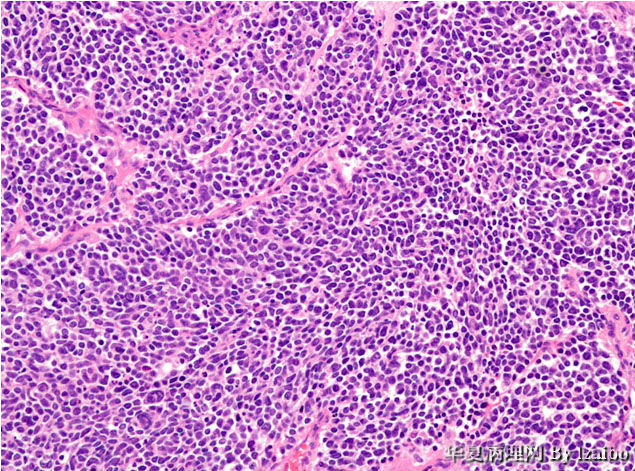

大体标本描述:肿块位于左肾上极,大小为15×9×8.5厘米。切面上,肿瘤为黄色,并具有散落的白色区域和偶尔出血区,没有明显坏死区。肿瘤非常接近血管,但大体上没有侵入到血管壁。大体上可见肿瘤侵犯输尿管和骨盆(图1和图2)。显微图片(图3-7)。

• 病例1-摘自UPMC Web Cases图3

图3